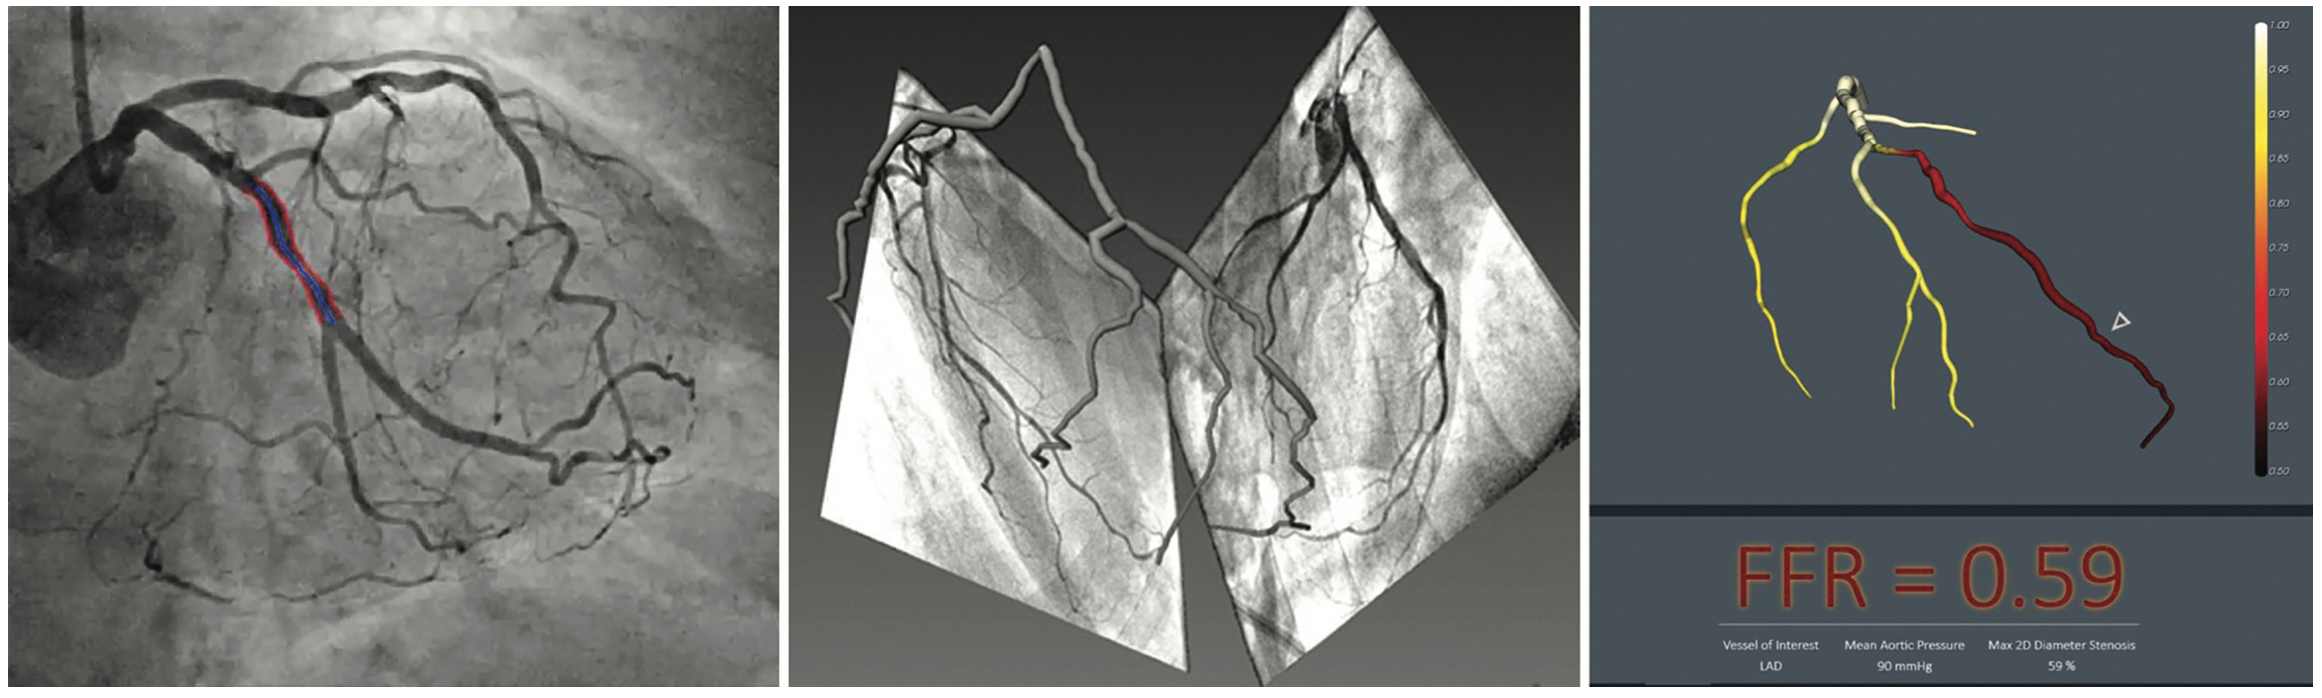

From www.hmpgloballearningnetwork.com

Noninvasive AngiographicDerived FFR Is Wireless Physiology Coming to Your Cath Lab Soon? Cath Lab Angiography Views For the beginner angiographer the anatomic landmarks formed by the spine, catheter and diaphragm provide information to discern which tomographic view from which the image is obtained. 100 to 200 rao and 150 to 200 caudal. Optimal views lao caudal and cranial; Common projections used in coronary angiography are left anterior oblique (lao), right anterior oblique (rao), postero. Course down. Cath Lab Angiography Views.